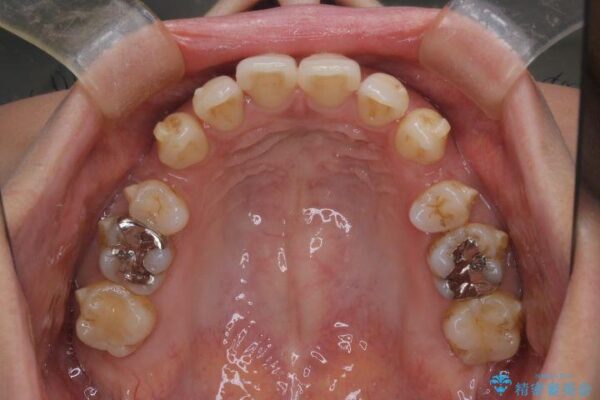

インビザラインにて抜歯矯正を行うと、高頻度で奥歯が咬み合わなくなります。

また、抜歯スペースに向けて奥歯が移動する際、必ず傾斜して移動するため、仕上がりの咬み合わせはワイヤー矯正と比べて明らかに劣ります。

抜歯スペースが閉じてからも咬みにくさ改善のためマウスピース矯正を継続するため、治療期間は長期化します。

治療途中

• 上顎前歯の突出を軽減 インビザラインによる抜歯矯正 治療途中画像